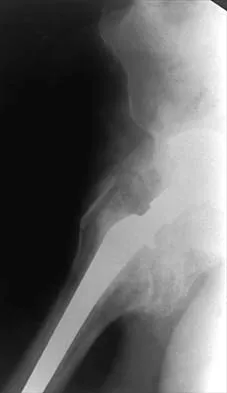

Figure 7 shows the AP radiograph of a 60-year-old man who has had pain in the thigh for past 6 months. History reveals that he underwent hip replacement 1 year ago. The radiographic changes are most likely the result of what process?

Explanation

The arrows in the radiograph point to circumferential radiolucencies that strongly support the diagnosis of septic loosening. Radiolucent lines that occur in such a short time are also typical of an infection. Garvin KL, Hanssen AD: Infection after total hip arthroplasty: Past, present, and future. J Bone Joint Surg Am 1995;77:1576-1588.